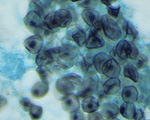

Paracoccidioides brasiliensis Pb03

|

[ Opisthokonta | Fungi | Dikarya | . . .

. . . | Onygenales incertae sedis | Paracoccidioides | Paracoccidioides brasiliensis ]

Picture Source

Picture Source

|

| Taxonomy: | Eukaryota | Opisthokonta | Fungi | Dikarya | Ascomycota | saccharomyceta | Pezizomycotina | leotiomyceta | Eurotiomycetes | Eurotiomycetidae | Onygenales | Onygenales incertae sedis | Paracoccidioides | Paracoccidioides brasiliensis |

| Synonym: | Loboa loboi, Aleurisma brasiliensis (obsolete), Blastomyces brasiliensis (obsolete), Coccidioides brasiliensis (obsolete), Coccidioides histosporocellularis (obsolete), Lutziomyces histosporocellularis (obsolete), Monilia brasiliensis (obsolete), Mycoderma brasiliensis (obsolete), Mycoderma histosporocellularis (obsolete), Zymonema brasiliense (obsolete) |

| Comment: | Paracoccidioides brasiliensisis dimorphic and the causative agent for paracoccidioidomycosis, a chronic granulomatous disease of mucous membranes, skin, and pulmonary system. In contrast to the other yeasts, particularly Blastomyces, Paracoccidioides has multiple buds, a thin cell wall, and a narrow base. |

|

|

|

Go to NCBI Taxonomy (482561) |

|

|

|  |

Encyclopedia of life |

|

|  |

Wikipedia |

| Publications: |

Desjardins CA, Champion MD, Holder JW et. al.

( 2011)

PLoS Genet 7, e1002345.

Felipe MS, Andrade RV, Arraes FB et. al.

( 2005)

J Biol Chem 280, 24706-14.

|

|